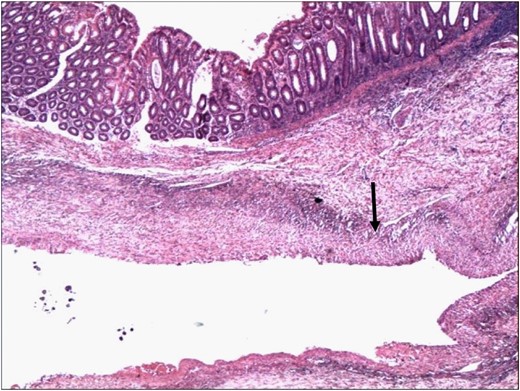

Histopathology confirmed the specimen to a SAA, with a 1 cm rupture through the colonic wall (Fig. 3A and B). On microscopic examination, the wall of the colon showed attenuation and loss of the muscle layers with bleeding into the lumen of the colon (Figs 4 and 5).

Wall of the colon showing attenuation and loss of the muscle layers. The wall of the aneurysm is indicated by the arrowhead (H&E 4×).